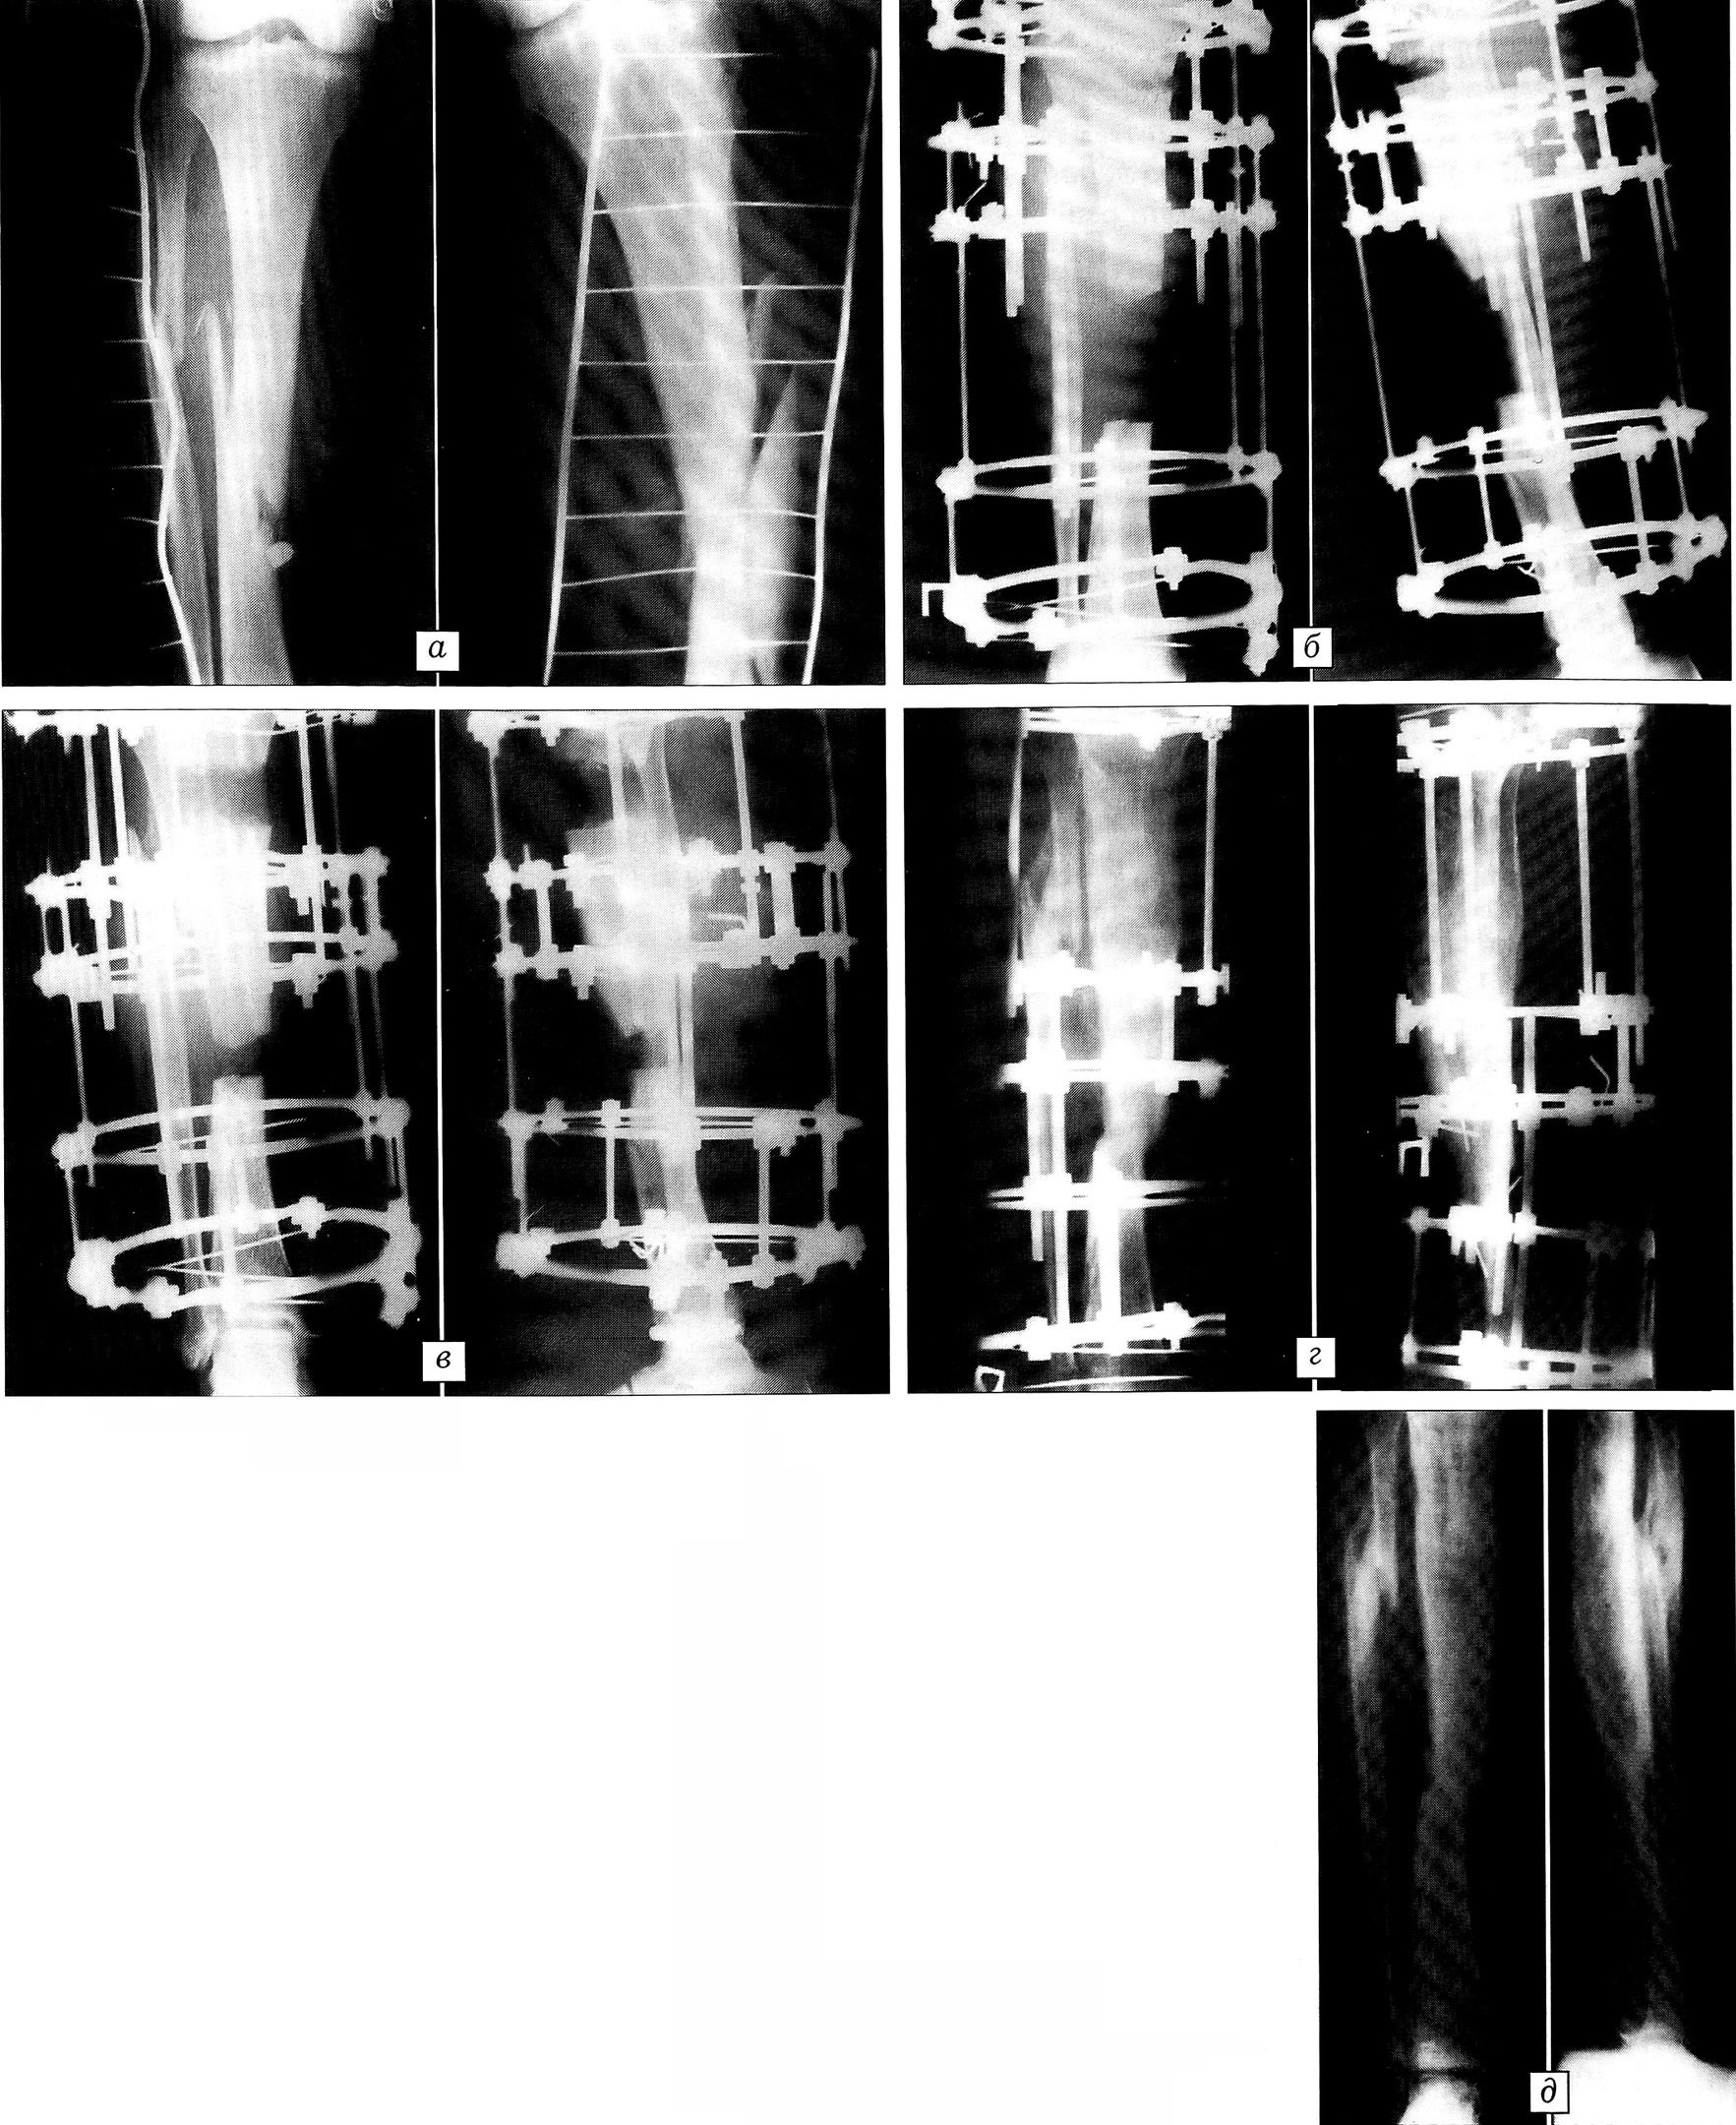

Больной С., 51 года, в результате разбойного нападения получил огнестрельные пулевые ранения мягких тканей обоих бедер, правой стопы, огнестрельный оскольчатый перелом костей правой голени в средней трети. Доставлен в одну из центральных районных больниц Московской области, где выполнена первичная хирургическая обработка огнестрельных ран с наложением глухих швов. На правую голень наложено скелетное вытяжение за пяточную кость. Через день с высокой температурой и выраженным отеком правой голени и бедра доставлен в приемное отделение ЦИТО (см. рисунок), где заподозрено развитие газовой инфекции (микробиологически не подтверждена). Произведены раскрытие защитных ран, «лампасные» разрезы с фасциотомией в области правого бедра и правой голени. Назначена массивная антибактериальная, дезинтоксикационная терапия. Раны промывались антисептиками, применялся ферментный препарат КФ. После стабилизации состояния пострадавшего (через 2 нед) выполнено оперативное вмешательство: некрэктомия мягкотканных ран правого бедра с дренированием, резекционная секвестрнекрэктомия концов отломков правой большеберцовой кости, чрескостный остеосинтез аппаратом Илизарова в компоновке для последующего билокального замещения дефекта средней трети большеберцовой кости, составившего после операции 8 см. После купирования гнойного процесса (спустя 2 нед) произведена кортикотомия проксимального отломка и начата дистракция в месте кортикотомии по 1 мм в сутки с целью получения дистракционного регенерата для замещения дефекта. В процессе лечения больной получал целенаправленную антибактериальную, иммунную и метаболитную терапию. Параллельно проводились реабилитационные мероприятия, направленные на профилактику развития контрактур в суставах поврежденной конечности. Достигнуто сращение перелома, дефект диафиза большеберцовой кости полностью замещен дистракционным регенератом. Аппарат Илизарова снят через 11 мес (см. рисунок). За один этап лечения у больного был ликвидирован остеомиелитический процесс, достигнуто сращение перелома, замещен дефект кости, полностью восстановлена функция поврежденной конечности.

Рентгенограммы больного С. 51 года. Огнестрельный оскольчатый перелом костей правой голени, осложненный гнойной инфекцией.а — до лечения; б — после резекционной секвестрнекрэктомии и кортикотомии проксимального отломка большеберцовой кости; в — в процессе замещения дефекта большеберцовой кости; г — перед снятием аппарата Илизарова: перелом большеберцовой кости сросся, дефект замещен дистракционным регенератом; д — после демонтажа аппарата.